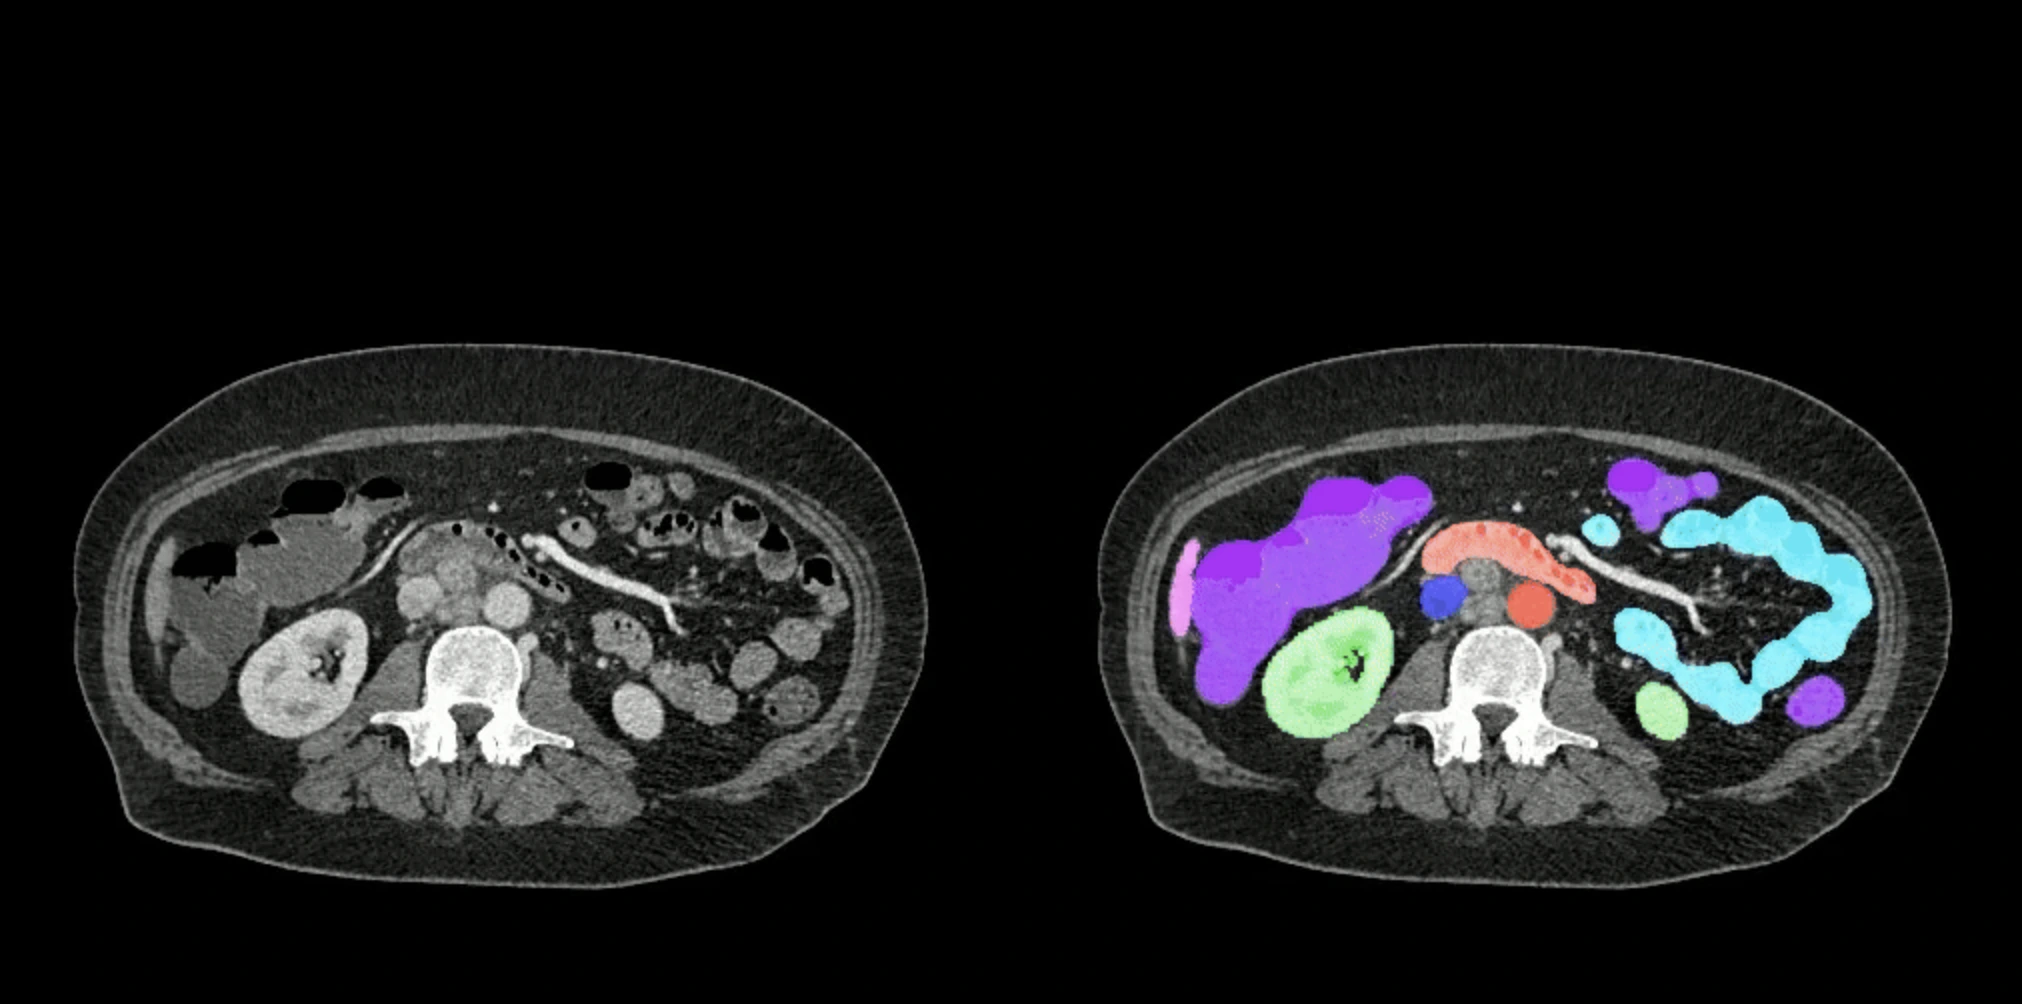

שתי סדרות של חתכי סריקות CT של הבטן – הסטנדרטית משמאל וסגמנטציית האיברים של AbdomenAtlas מימין.

כאן נכנסת לתמונה AbdomenAtlas, פרויקט חדשני שפותח על ידי צוות חוקרים מאוניברסיטת ג'ונס הופקינס, בראשות הפרופסור אלן יואל. מדובר במאגר הדמיות CT הגדול ביותר שנוצר אי פעם, הכולל מעל 45,000 סריקות של 142 מבנים אנטומיים שונים שנאספו מ-145 בתי חולים ברחבי העולם. בהשוואה למאגר הנתונים הקודם בתחום (TotalSegmentator V2), AbdomenAtlas גדול יותר פי 36 ומאפשר דיוק חסר תקדים בזיהוי מבנים בבטן.

החוקרים שילבו שלושה מודלים שונים של AI, אשר אומנו מראש על נתונים ציבוריים מסומנים של סריקות בטן. מודלים אלו חזו את המיקום והמבנה של איברים בסריקות לא מסומנות, ולאחר מכן השתמשו במפות צבעוניות להדגשת אזורים שבהם נדרש תיקון אנושי. בשיטה זו, הצוות השיג האצה של פי 500 בתהליך הסימון של איברים, ופי 10 בזיהוי גידולים.